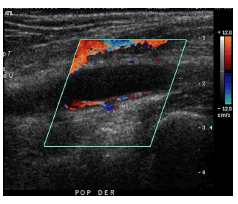

Se trata de un paciente de sexo masculino de 57 años de edad, con antecedentes de tabaquismo crónico (56 paquetes por año) suspendido 14 años atrás y dislipidemia. Consultó por claudicación con la caminata de 50 metros y paresia del pie derecho. En el estudio etiológico, la ecografía Doppler de la extremidad inferior demostró una lesión quística fusiforme de probable origen intraparietal, localizada en el aspecto posterior de la arteria poplítea, de 2,5 cm en su eje mayor, avascular al Doppler de color (figura 1).

Junto con la historia clínica, los estudios de imágenes son fundamentales para establecer el diagnóstico. La ecografía es un método útil en la evaluación de la esta enfermedad al estar ampliamente disponible, no ser invasiva y ser de bajo costo 9. Permite visualizar el quiste como una estructura anecogénica o hipoecogénica en la pared del vaso, sin flujo demostrable en el modo Doppler, así como la estenosis arterial secundaria 10.